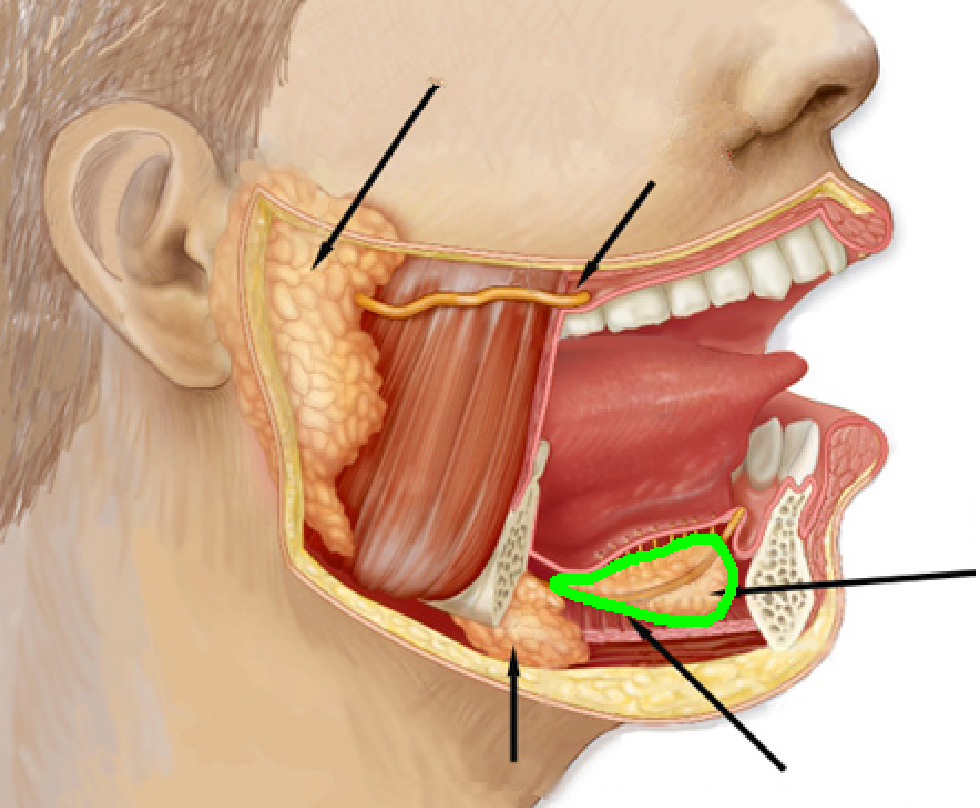

Sublingual gland

Submandibular gland

Submandibular ducts

Sublingual ducts